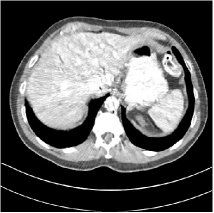

Refer to caption WavResNet [11]Refer to caption WavResNet [11]Refer to caption WavResNet [11]Refer to caption Momentum-Net (SimpleCNN)Refer to caption Momentum-Net (SimpleCNN)Refer to caption Momentum-Net (SimpleCNN)Refer to caption Momentum-Net (SimpleCNN-RSN)Refer to caption Momentum-Net (SimpleCNN-RSN)Refer to caption Momentum-Net (SimpleCNN-RSN)Refer to caption Momentum-Net (Dn-RSN)Refer to caption Momentum-Net (Dn-RSN)Refer to caption Momentum-Net (Dn-RSN)Refer to caption ReferenceRefer to caption ReferenceRefer to caption Reference

Fig. 3: Three examples (from top to bottom) of the reconstructed testing images using Momentum-Net with SimpleCNN (the second column), with SimpleCNN-RSN (the third column), and with Dn-RSN (the fourth column). The compared WavResNet denoised images are shown in the first column, and the reference images are in the fifth column. See their FBP images in Fig. 4.

Fig. 2 shows that the proposed Momentum-Net with SimpleCNN decreases RMSE dramatically in the first 30 layers, and tends to converge in 50 layers. The Momentum-Net reduces the mean RMSE value by 4.5 HU and gives smaller standard deviations in RMSE, compared to WavResNet, as reported in Table 1. This implies that the proposed Momentum-Net with SimpleCNN can improve both the accuracy and stability of low-dose CT image reconstruction than a state-of-the-art image denoising deep NN, WavResNet. The proposed Momentum-Net with SimpleCNN better removes noise and streak artifacts than WavResNet. It also provides clearer reconstructions of some details; see, in Fig. 3, the boundaries shown in the zoomed region at the top-right corner in the first example, the arrow pointed structures in zoomed areas of the second example, and the arrow pointed tissues in the left zoomed region in the third example.

We show the reconstructed examples by Momentum-Net with SimpleCNN-RSN and Dn-RSN in the third and fourth columns of Fig. 3 respectively. Comparing the first three and the last columns in Fig. 3, we observe that Momentum-Net with SimpleCNN-RSN provides generally noisier reconstructions than WavResNet and Momentum-Net with SimpleCNN. However, Momentum-Net with SimpleCNN-RSN sometimes can provide clearer details than WavResNet. For example, in the right zoomed box of the second example, Momentum-Net with SimpleCNN-RSN shows better reconstruction quality for the arrow pointed structures than WavResNet, and in the left zoomed box in the third row, the former gives clearer small tissues marked by red arrows than the latter. Table 1 reports that Momentum-Net with SimpleCNN-RSN is approximately 2.9 RMSE (HU) higher than WavResNet, while it has smaller standard deviations. This implies that Momentum-Net with SimpleCNN-RSN is more stable than WavResNet, although it may not provide better image qualities. Momentum-Net with Dn-RSN, however, provides the worst visual and numerical results among the compared four methods in this paper.